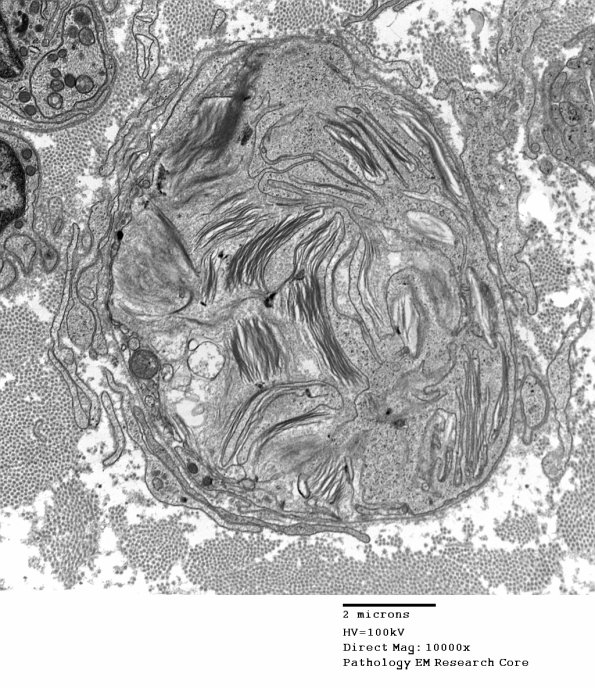

Washington University Experience | PERIPHERAL NEUROPATHY | 4 AXONAL DEGENERATION | 3 Electron Microscopy | 2E7 Axonal Degeneration (Case 12) 027 - Copy

2E7,8 In this case delicate macrophage pseudopods (arrow, 2E8) are closely apposed to the debris containing Schwann cell cytoplasm, possibly removing it.